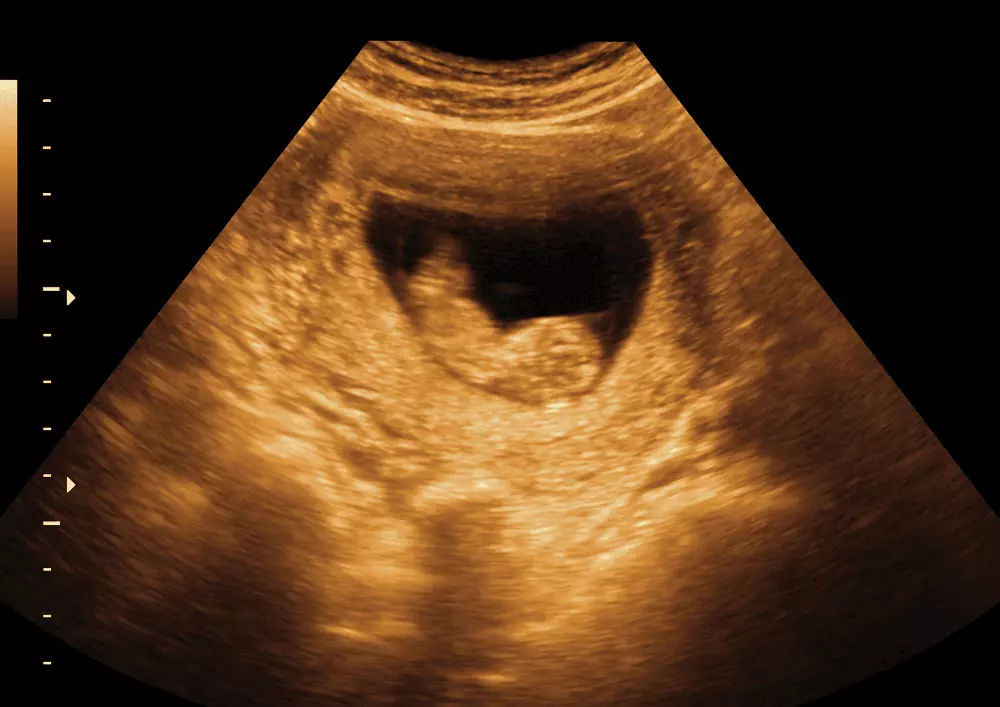

Zaburzenie rozwojowe powstałe na skutek malformacji łuku oskrzelowego, znane jako zespół Pierre Robin, zostało opisane po raz pierwszy w 1923 roku. Nazwa „zespół” funkcjonowała do 1976 roku, kiedy to ze względu na charakter nieprawidłowości wprowadzono termin sekwencja Pierre Robin, jak tłumaczy doktor nauk biologicznych Anna Żebryk-Stopa. W tym przypadku owym specyficznym zaburzeniem jest kaskada nieprawidłowości anatomicznych, wynikająca z pojedynczego defektu rozwojowego i wtórnych zmian strukturalnych lub funkcjonalnych innych narządów. Sekwencja Pierre Robin charakteryzuje się pierwotną wadą, jaką jest mikrognatia. Zespołowi Pierre Robin towarzyszy niedorozwój żuchwy, duży język, zaburzenia oddechu i rozszczep podniebienia, dlatego ćwiczenia oddechowe są niezwykle istotne w terapii pacjenta z tą rzadką wadą wrodzoną.